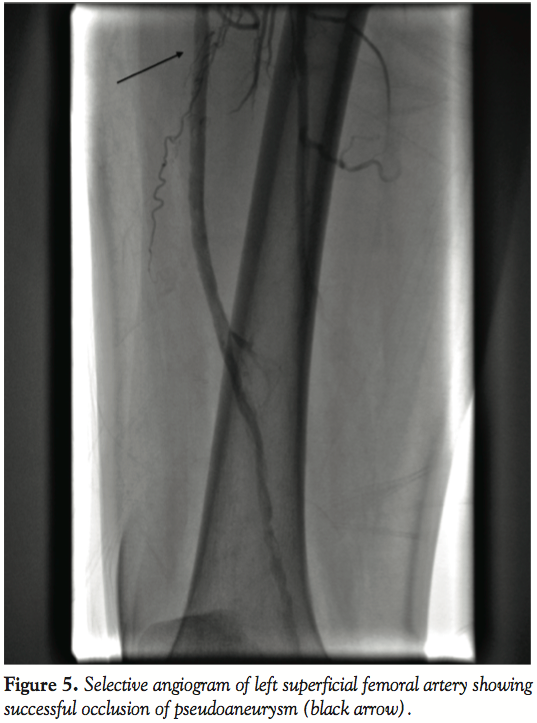

Case Report. A 70-year-old white male with history of hypertension, hyperlipidemia, coronary artery disease, prior bypass surgery, tobacco abuse, and severe peripheral vascular disease was seen in-clinic for class IV claudication with ischemic rest pain. Patient had been on appropriate medical management including an exercise regimen for approximately 9 months with no improvement in symptoms. He underwent a peripheral angiogram that showed chronic total occlusion (CTO) of the right and SFA (Figure 1). Since the left SFA

was more symptomatic, we proceeded with a left SFA intervention. After anticoagulation with bivalirudin, the lesion was crossed with a combination of a Terumo glidewire (Terumo Corporation) and a Confianza Pro wire (Abbott Vascular) with Trailblazer catheter (ev3 Endovascular) support. After confirmation of the distal end being in the true lumen by contrast injection through the Trailblazer catheter, atherectomy was performed with a TurboHawk LX-C device (ev3) followed by balloon angioplasty with a 5.0 mm x 120 mm EverCross balloon (ev3). There were no immediate complications and successful reduction of stenosis to <10% (Figure 2).